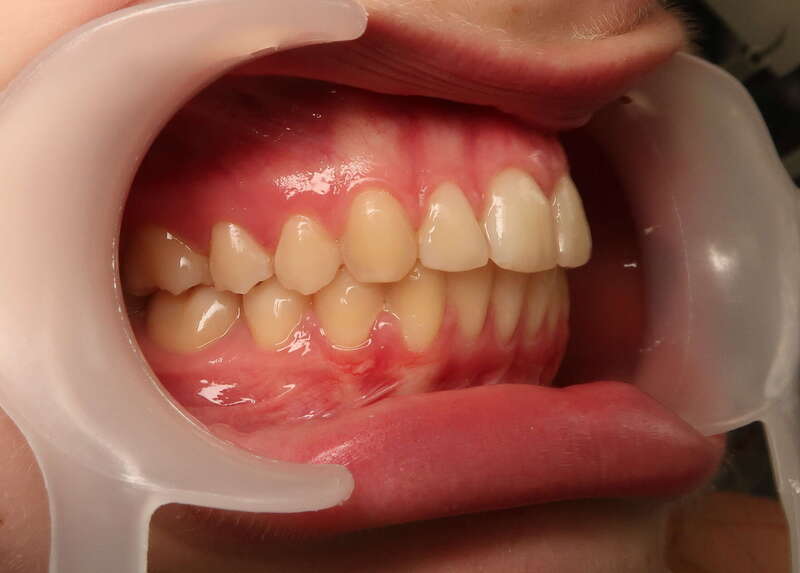

Cas n°1 traité par aligneurs - adolescent

Ce cas d’une adolescente illustre la correction d'une Classe II avec supraclusion par aligneurs. La stratégie thérapeutique a reposé sur une distalisation séquentielle de l'arcade supérieure. Ce mouvement précis a permis de reculer les dents maxillaires étape par étape pour annuler le surplomb (overjet) sans extractions.

Résultats clés :

• Correction fonctionnelle : Retour à un engrènement de Classe I stable et correction du recouvrement vertical.

• Esthétique restaurée : Harmonisation globale du sourire et du profil.

• Approche moderne : Un traitement discret, confortable et hautement prévisible.

Le résultat final montre une occlusion saine et un sourire parfaitement aligné, garantissant une santé dentaire et articulaire optimale pour l'avenir.

Avant

Après